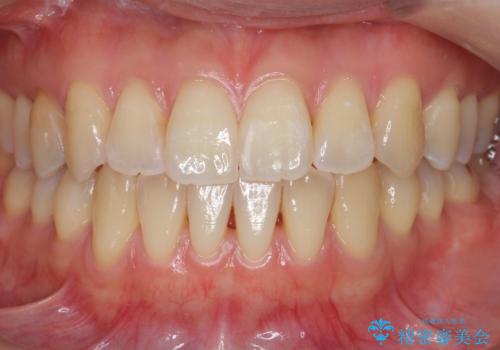

[ 前歯のねじれ・がたつき ] マウスピース矯正

![[ 前歯のねじれ・がたつき ] マウスピース矯正の症例 治療前](https://seimitsushinbi.jp/wp/wp-content/uploads/2024/02/4007c6479f6bce11863dcdd32ed5e39b-500x350.jpg?v=1708502552)

![[ 前歯のねじれ・がたつき ] マウスピース矯正の症例 治療後](https://seimitsushinbi.jp/wp/wp-content/uploads/2024/02/e7a01485e4f4dd0da04705fde4cc34cc-500x350.jpg?v=1708502585)